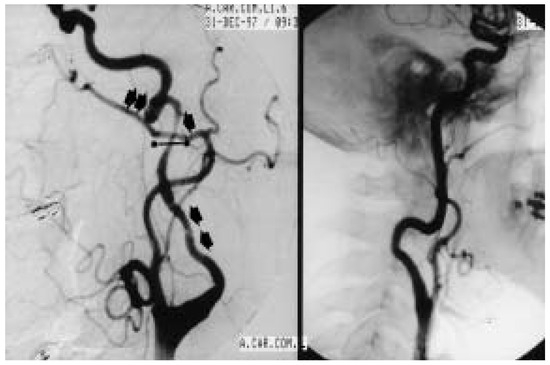

Rarely, adult moyamoya disease presents with recurrent migraine-like headaches during a long course.We report the case of a 31-year-old woman with moyamoya disease and migraine-like headaches, with a 13-year history. Physical examination showed no neurologic deficits. Magnetic resonance angiography (MRA) and digital subtraction [...] Read more.

Rarely, adult moyamoya disease presents with recurrent migraine-like headaches during a long course.We report the case of a 31-year-old woman with moyamoya disease and migraine-like headaches, with a 13-year history. Physical examination showed no neurologic deficits. Magnetic resonance angiography (MRA) and digital subtraction angiography (DSA) showed occlusion of the right internal carotid artery (ICA), severe stenosis of the left ICA, and abnormal vascular network at the base of the brain. The calcium channel blocker, nimodipine, was introduced in order to prevent further symptoms. After the introduction of nimodipine, no further headache, weakness and numbness of the left hand occurred in this patient. This suggests that migraine-like headaches may be caused by moyamoya disease and that nimodipine may have a beneficial effect on this condition. Full article